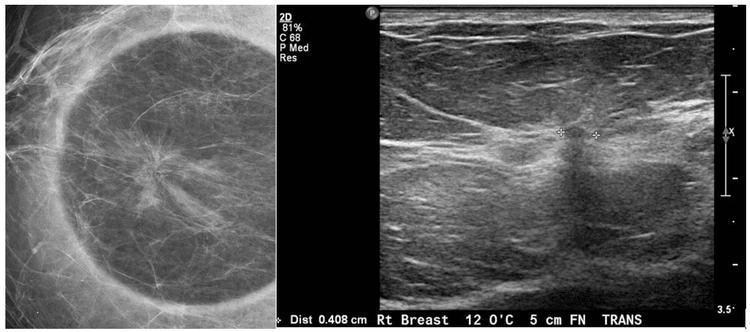

Đặc điểm hình ảnh sẹo tỏa tia của vú

Bài viết bởi Thạc sĩ, Bác sĩ Tống Dịu Hường - Khoa Chẩn đoán hình ảnh - Bệnh viện Đa khoa Quốc tế Vinmec Nha Trang Sẹo tỏa tia là một bệnh lý tăng sinh lành tính của vú. Các...